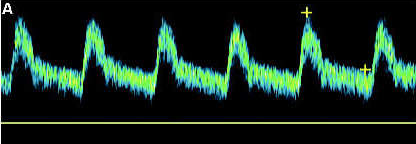

Patient admitted with sudden onset of LT sided weakness and aphasia x 48 hours. Carotid duplex ordered and you obtain this image of RT ICA.

1. Considering patient symptoms, is this a TIA? Why or why not?

2. Considering velocities, what does this image indicate?

3. Describe waveform down stream from this current location.

No because its more than 24 hours

That there is a hemodynamically significant stenosis because the velocities are pretty high at 367.3 cm/s

would be a tardus parvus waveform (slow rise, slow fall)